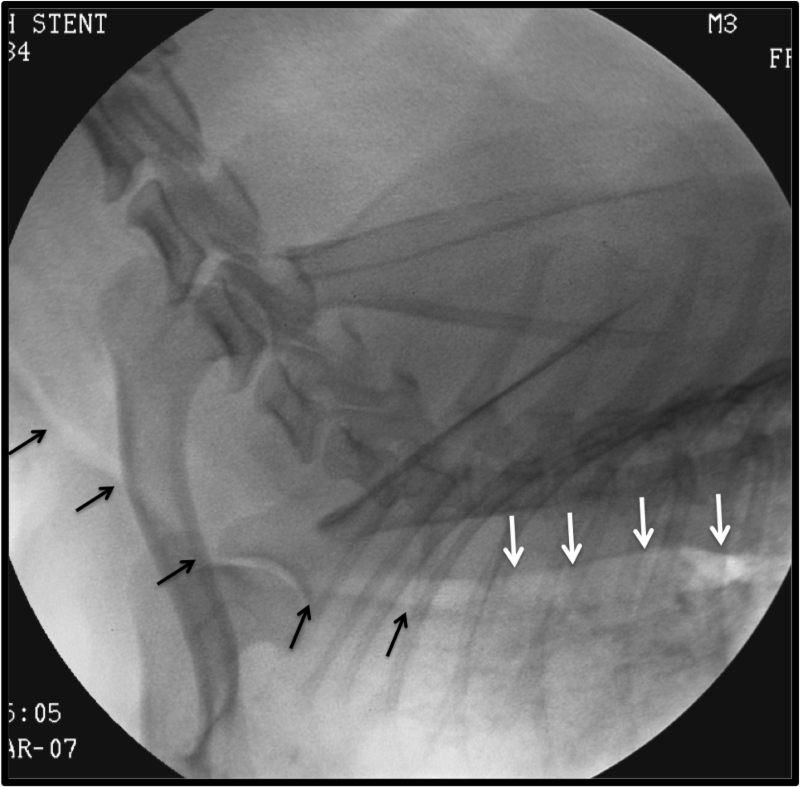

Tracheal Collapse Medical Management Versus Implantable Stents

From vhc.missouri.edu